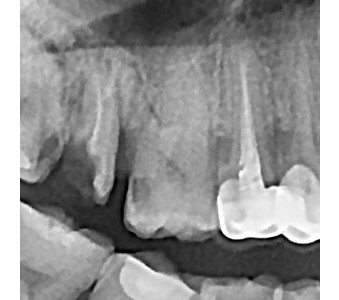

결과로 증명합니다.

국제모아치과의

실제 임상 증례